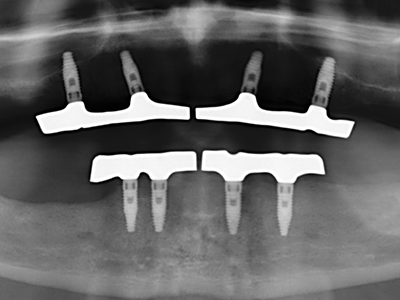

Für die Entnahme von Implantaten ist die Präparation eines vestibulären Knochendeckels möglich, der nach Entfernung der Implantatschraube refixiert wird und auf diesem Wege die Kontur des Alveolarfortsatzes erhält.